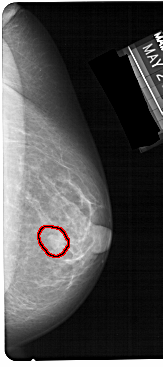

A_1304_1.LEFT_MLO

LEFT_MLO LINES 5491 PIXELS_PER_LINE 2521 BITS_PER_PIXEL 12 RESOLUTION 43.5 NON_OVERLAY

FILE: A_1304_1.RIGHT_MLO.OVERLAY

TOTAL_ABNORMALITIES 1

ABNORMALITY 1

LESION_TYPE MASS SHAPE OVAL MARGINS CIRCUMSCRIBED

ASSESSMENT 4

SUBTLETY 4

PATHOLOGY BENIGN

TOTAL_OUTLINES 1

BOUNDARY